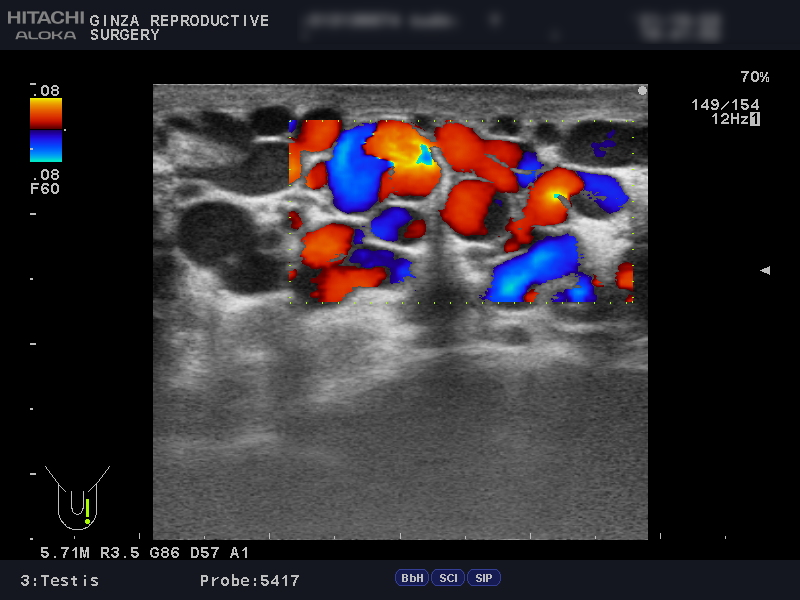

精索静脈瘤の診断には、エコー検査を用います。

エコー検査では、精巣内や精巣上体の観察と精索静脈瘤の診断を行います。同時に不妊や別の病気と関連している、以下のような異常がないかどうかも詳しく確認します。

以下は、当院でエコー検査を受けられた患者さんの画像です。

精索静脈径が3mm以上だと治療を推奨されるところ、左側の画像では4.5~6.8mmで、血管が明らかに拡張しています。

安静にしていてもドップラー法で顕著な逆流が観察でき、腹圧でさらに増強していました。ドップラー法は、血液の逆流を確認する方法です。

上の画像検査結果より、グレード3の左精索静脈瘤であると診断されました。